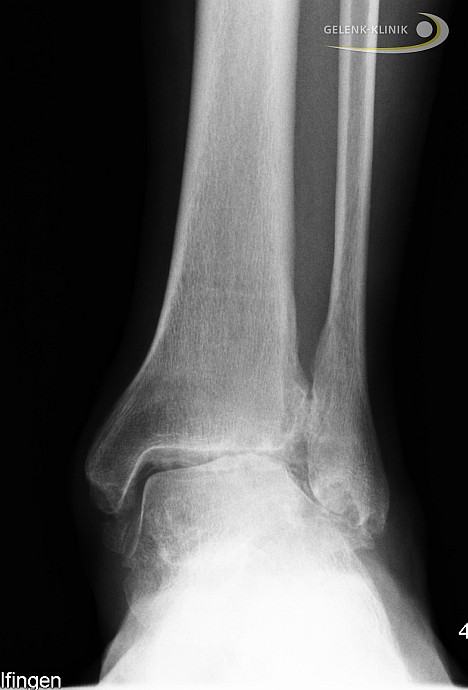

Im Röntgenbild ist die Knorpelschicht nur indirekt durch den Abstand der Knochen im Gelenk sichtbar. Sie bildet den sogenannten Gelenkspalt. Ist diese Schicht noch ausgeprägt, halten die Gelenkpartner im Sprunggelenk einen im Röntgenbild deutlich sichtbaren Abstand zueinander.

Schwindet der Gelenkspalt durch Knorpelabrieb und Arthrose, resultiert eine erhöhte Belastung des angrenzenden Knochens. Die Folge ist vermehrter Knorpelabrieb.

Eine Verschmälerung des Gelenkspaltes im Sprunggelenk weist indirekt auf eine Knorpelschädigung hin und ist damit ein frühes Zeichen der Sprunggelenksarthrose. Resultierend aus dem Knorpelschaden kommt es zu einer Anpassungsreaktion des umliegenden Knochens. Eine Verdichtung des Knochens (Sklerosierung) am Sprunggelenk ist die Folge des Knorpelabbaus.

Zeichen einer fortgeschrittenen Sprunggelenksarthrose im Röntgenbild

Der Gelenkspalt des Sprunggelenkes verschwindet zunehmend und der gelenknahe Knochen verdichtet sich immer stärker. Durch die vermehrte Belastung reagiert der Knochen im Randbereich mit der Ausbildung von Knochenanbauten (sog. Osteophyten). Die Druckzunahme im Knochen kann im Verlauf zu blasenförmigen Knochenauflösungen (sog. Geröllzysten oder Geoden) führen. Dies sind Hohlräume im Knochen, die durch Knochentod (Osteonekrose) entstehen. Als letztes Zeichen einer Sprunggelenksarthrose verformen sich die Gelenkpartner, weil die Belastungslinien des Gelenkes sich verändern.

Am oberen Sprunggelenk flacht das Sprungbein (Talus) häufig ab und der Knochen gleitet nach vorne. Durch diese Veränderungen resultieren zunehmende Einschränkungen, die sich weiterhin auf die benachbarten Gelenke auswirken können.